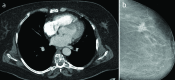

Objective: Although mammography is the primary imaging method of the breast, incidental benign and malignant breast lesions are increasingly being detected on computed tomographies (CTs) performed to detect different pathologies. Therefore, the detection and accurate identification of these lesions is important. In this study, we aimed to evaluate the frequency, morphological features, and results of incidental breast lesions on CTs performed for the detection of extramammarian pathologies.

Results: The study population consisted of 33 women whose mean age was 55±1.38 (37-78) years. Of the 33 women, 12 (36%) had malignant and 21 (64%) had benign or normal findings. The most common malignant lesion was invasive ductal carcinoma, and the most common benign lesion was fibroadenoma. Ill-defined contour and lymphadenopathy in malignant lesions and well-defined contour in benign lesions were the most important CT findings.

Conclusion: Breast must be carefully evaluated if it is included in the scans. An accurate report of breast lesions gives an opportunity for early diagnosis and treatment.